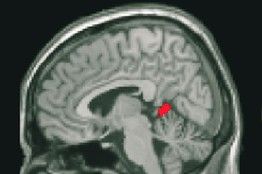

圖:研究人員發(fā)現(xiàn),隨著大腦內(nèi)與語(yǔ)言技能有關(guān)的區(qū)域發(fā)生改變,語(yǔ)言智商也會(huì)相應(yīng)地發(fā)生巨大的改變,而非語(yǔ)言智商是隨著與手部動(dòng)作的相關(guān)一個(gè)區(qū)域變化而變化的。

研究人員還發(fā)現(xiàn),在智商變化的同時(shí),大腦內(nèi)與智力技能有關(guān)的區(qū)域也會(huì)相應(yīng)發(fā)生微小的物理變化,盡管他們還無(wú)法給出明確的原因和影響。

為了更好地理解智力,普賴斯和她的同事研究了33位健康的英國(guó)青少年,這些人的智商最初在80──140之間。他們?cè)?004年對(duì)這批志愿者進(jìn)行了標(biāo)準(zhǔn)化智力測(cè)試,在2008年又進(jìn)行了一次測(cè)試,以此來(lái)涵蓋這些人青春期的高峰年份。研究人員用機(jī)能性磁共振成像儀來(lái)監(jiān)測(cè)這批青少年大腦結(jié)構(gòu)的細(xì)微變化。通過(guò)分別分析受測(cè)者的語(yǔ)言智商成績(jī)和非語(yǔ)言智商成績(jī),研究人員發(fā)現(xiàn),這些基本智力方面可能會(huì)發(fā)生明顯變化。